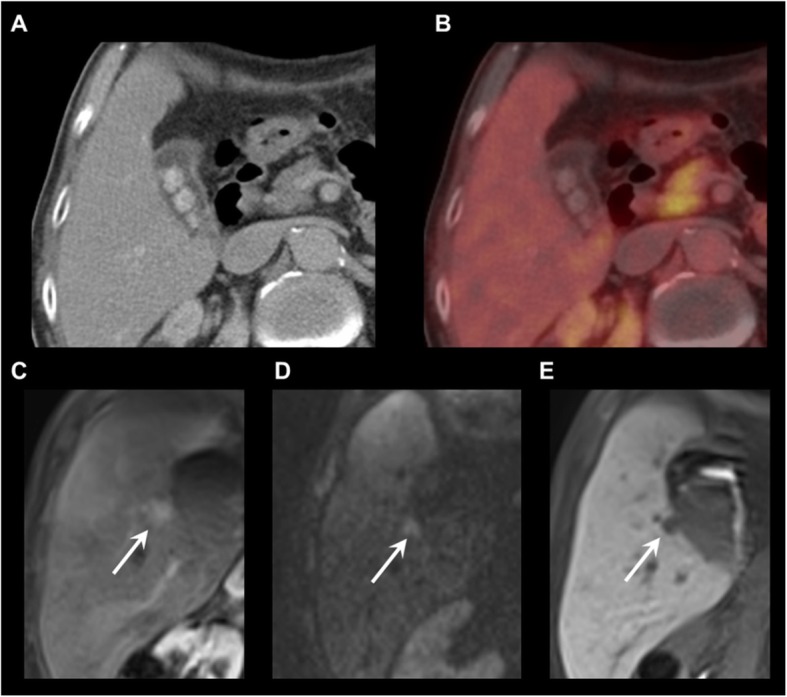

Fig. 4.

Detection of an 18F-DOPA-PET/CT occult liver metastasis on gadoxetic acid-enhanced MRI. a Contrast-enhanced CT. b 18F-DOPA-PET/CT (fusion image). c T1 GRE fs, arterial phase. d DWI, b800. e T1 GRE fs, hepatobiliary phase. 18F-DOPA-PET/CT shows no liver lesion. MRI reveals an 18F-DOPA-PET/CT-occult, hypervascular metastasis in liver segment V (C-E, arrows)